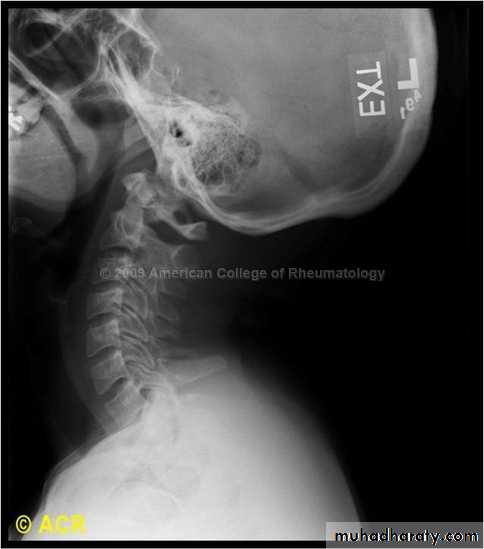

DIAGNOSISX RAY

Anterio posterior X ray radiograph.lateral radiographs with the head in flexion and extension may revealinstability that is not shown in the routine lateral film.

oblique views

at 45° are especially helpfula special projection

through the open mouth.Computed tomography (CT)

and magnetic resonance imaging (MRI).